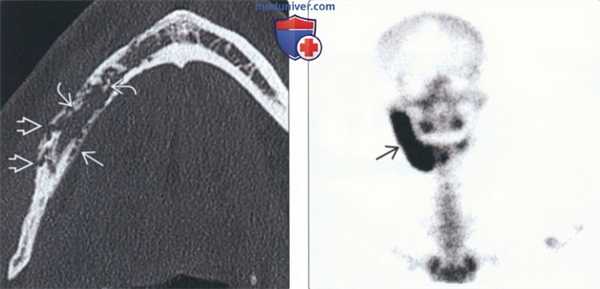

(Слева) На аксиальной КТ в костном окне определяются плохо отграниченные, «изъеденные молью» участки деструкции у пациента с остеомиелитом нижней челюсти справа. Кортикальная пластинка в нескольких местах разрушена. Обратите внимание на периостальные наложения на язычной поверхности и признаки секвеарации, помогающие отличить остеомиелит от злокачественной опухоли. У этого пациента явные изменения мягких тканей отсутствуют.

(Справа) На изображении (остеосцинтиграфия с Тс-99m МДФ) у пациента с остеомиелитом нижней челюсти справа определяется выраженное накопление радиофармпрепарата.

6. Сцинтиграфия:

• Остеосцинтиграфия с Tc-99m МДФ: чувствительный, не специфичный метод:

о Позволяет выявить ранние поражения до их обнаружения рентгеновскими методами

о Применима при подозрении на мультифокальное заболевание (синдром САФО, SAPHO: синовит, акне, пустулез, гиперостоз, остеит)

о ОФЭКТ помогает оценить локализацию поражения костей